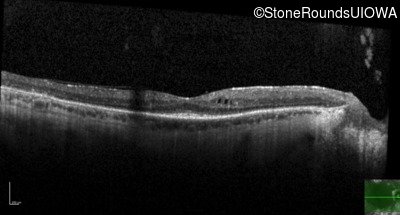

Optical Coherence Tomography - Right - 20/25 -1

Exemplar / OCT Stack

OCT Stack